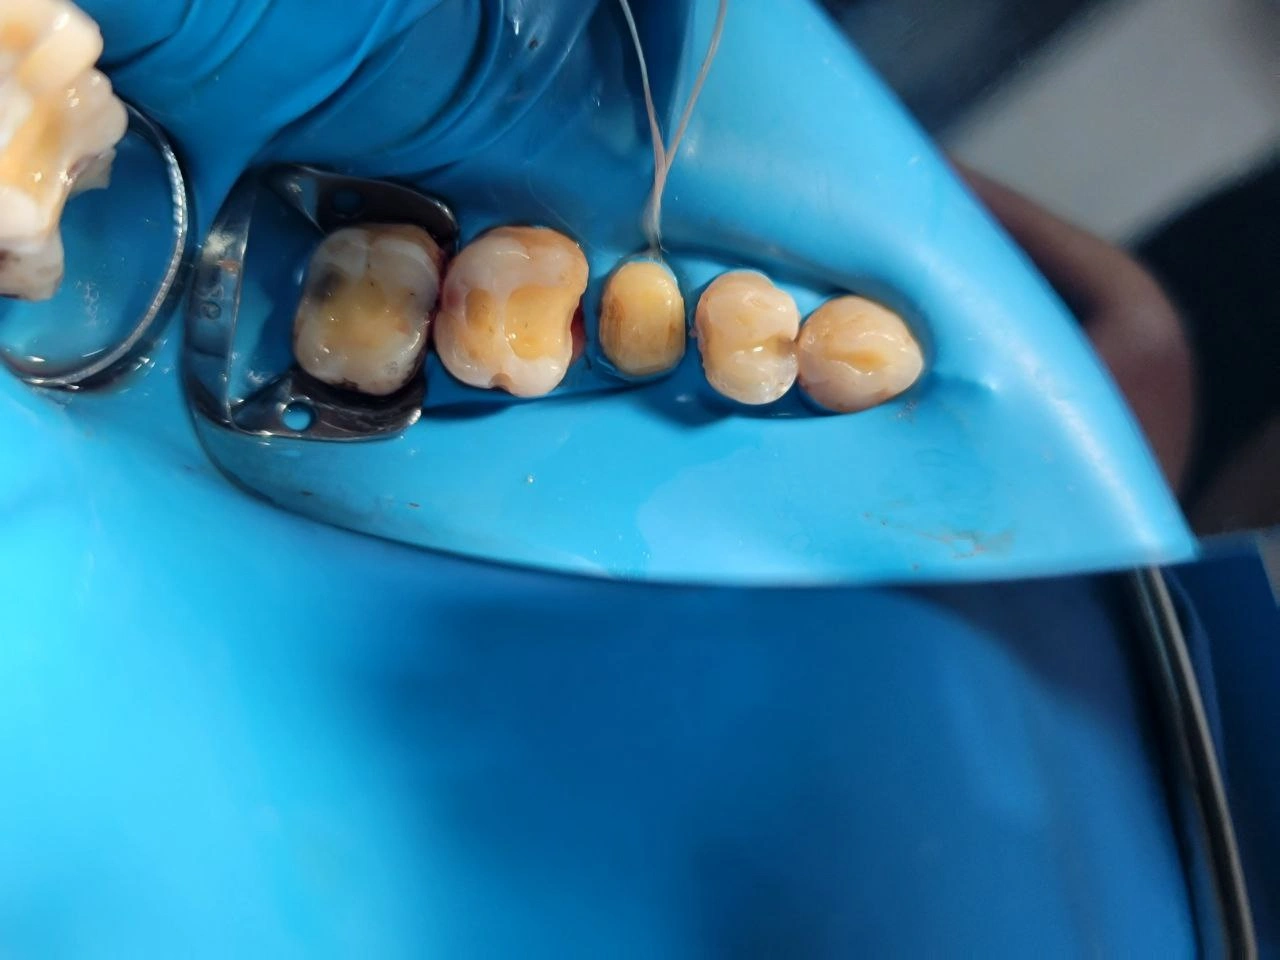

View under rubber dam isolation after the complete removal of the old restorations and carious tissue, ready for the bonding procedure.